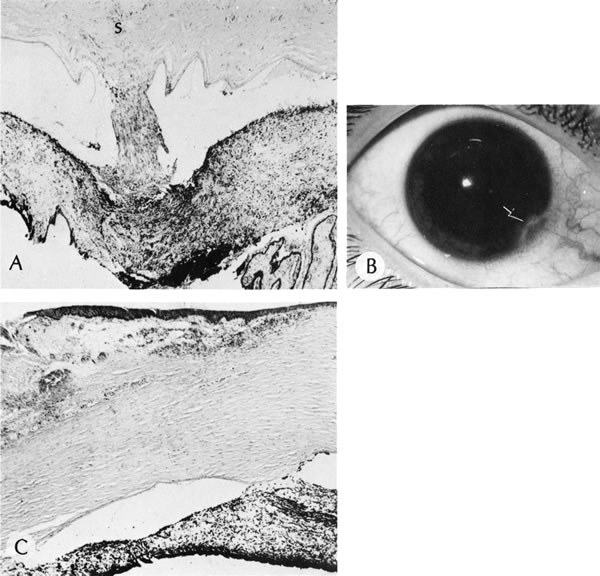

AXENFELD'S ANOMALY

Isolated Axenfeld's anomaly (posterior embryotoxon) consists of a clinically prominent Schwalbe's line (terminal end of Descemet's membrane) plus a variable number of iris processes extending from the peripheral iris to Schwalbe's line (Fig. 6). The condition is most likely a developmental arrest, late in gestation, of tissues derived from neural crest cells.66 The line appears as a deep linear opacity of the peripheral cornea of variable prominence and extent and is most often found temporally. The prevalence rate is approximately 15% to 25%.67,68 No race or sex predilection exists. Although the majority of the eyes are normal, an associated partial iris coloboma and other anomalies may occur.68 Axenfeld's anomaly may be associated with non-ocular abnormalities as part of Axenfeld-Rieger's syndrome (see later).

Fig. 6. Axenfeld's anomaly (posterior embryotoxin). A. The only abnormality visible from the 2-o'clock to 4-o'clock positions adjacent to the limbus is a “ropy” corneal opacity. The other eye is normal. B. A corneal opacity is present over 360 degrees near the limbus at the level of Descemet's membrane. C. Scanning electron micrograph shows the iris processes spanning the angle and attaching to the anteriorly displaced Schwalbe's ring. Artifactually broken ends of the iris processes are indicated by the arrows. D. Macroscopic appearance of the iris processes attaching to Schwalbe's ring. E. Iris processes attach to the anteriorly displaced Schwalbe's ring. (Courtesy of SEI Photoarchives.)

Histologically, Axenfeld's anomaly consists of dense collagen and ground substance covered by a monolayer of flattened endothelial or spindle-shaped cells at the terminal end of Descemet's membrane. The endothelium is contiguous with the endothelium covering the trabecular beams.68 Associated iris processes are composed of normal-appearing iris stroma.